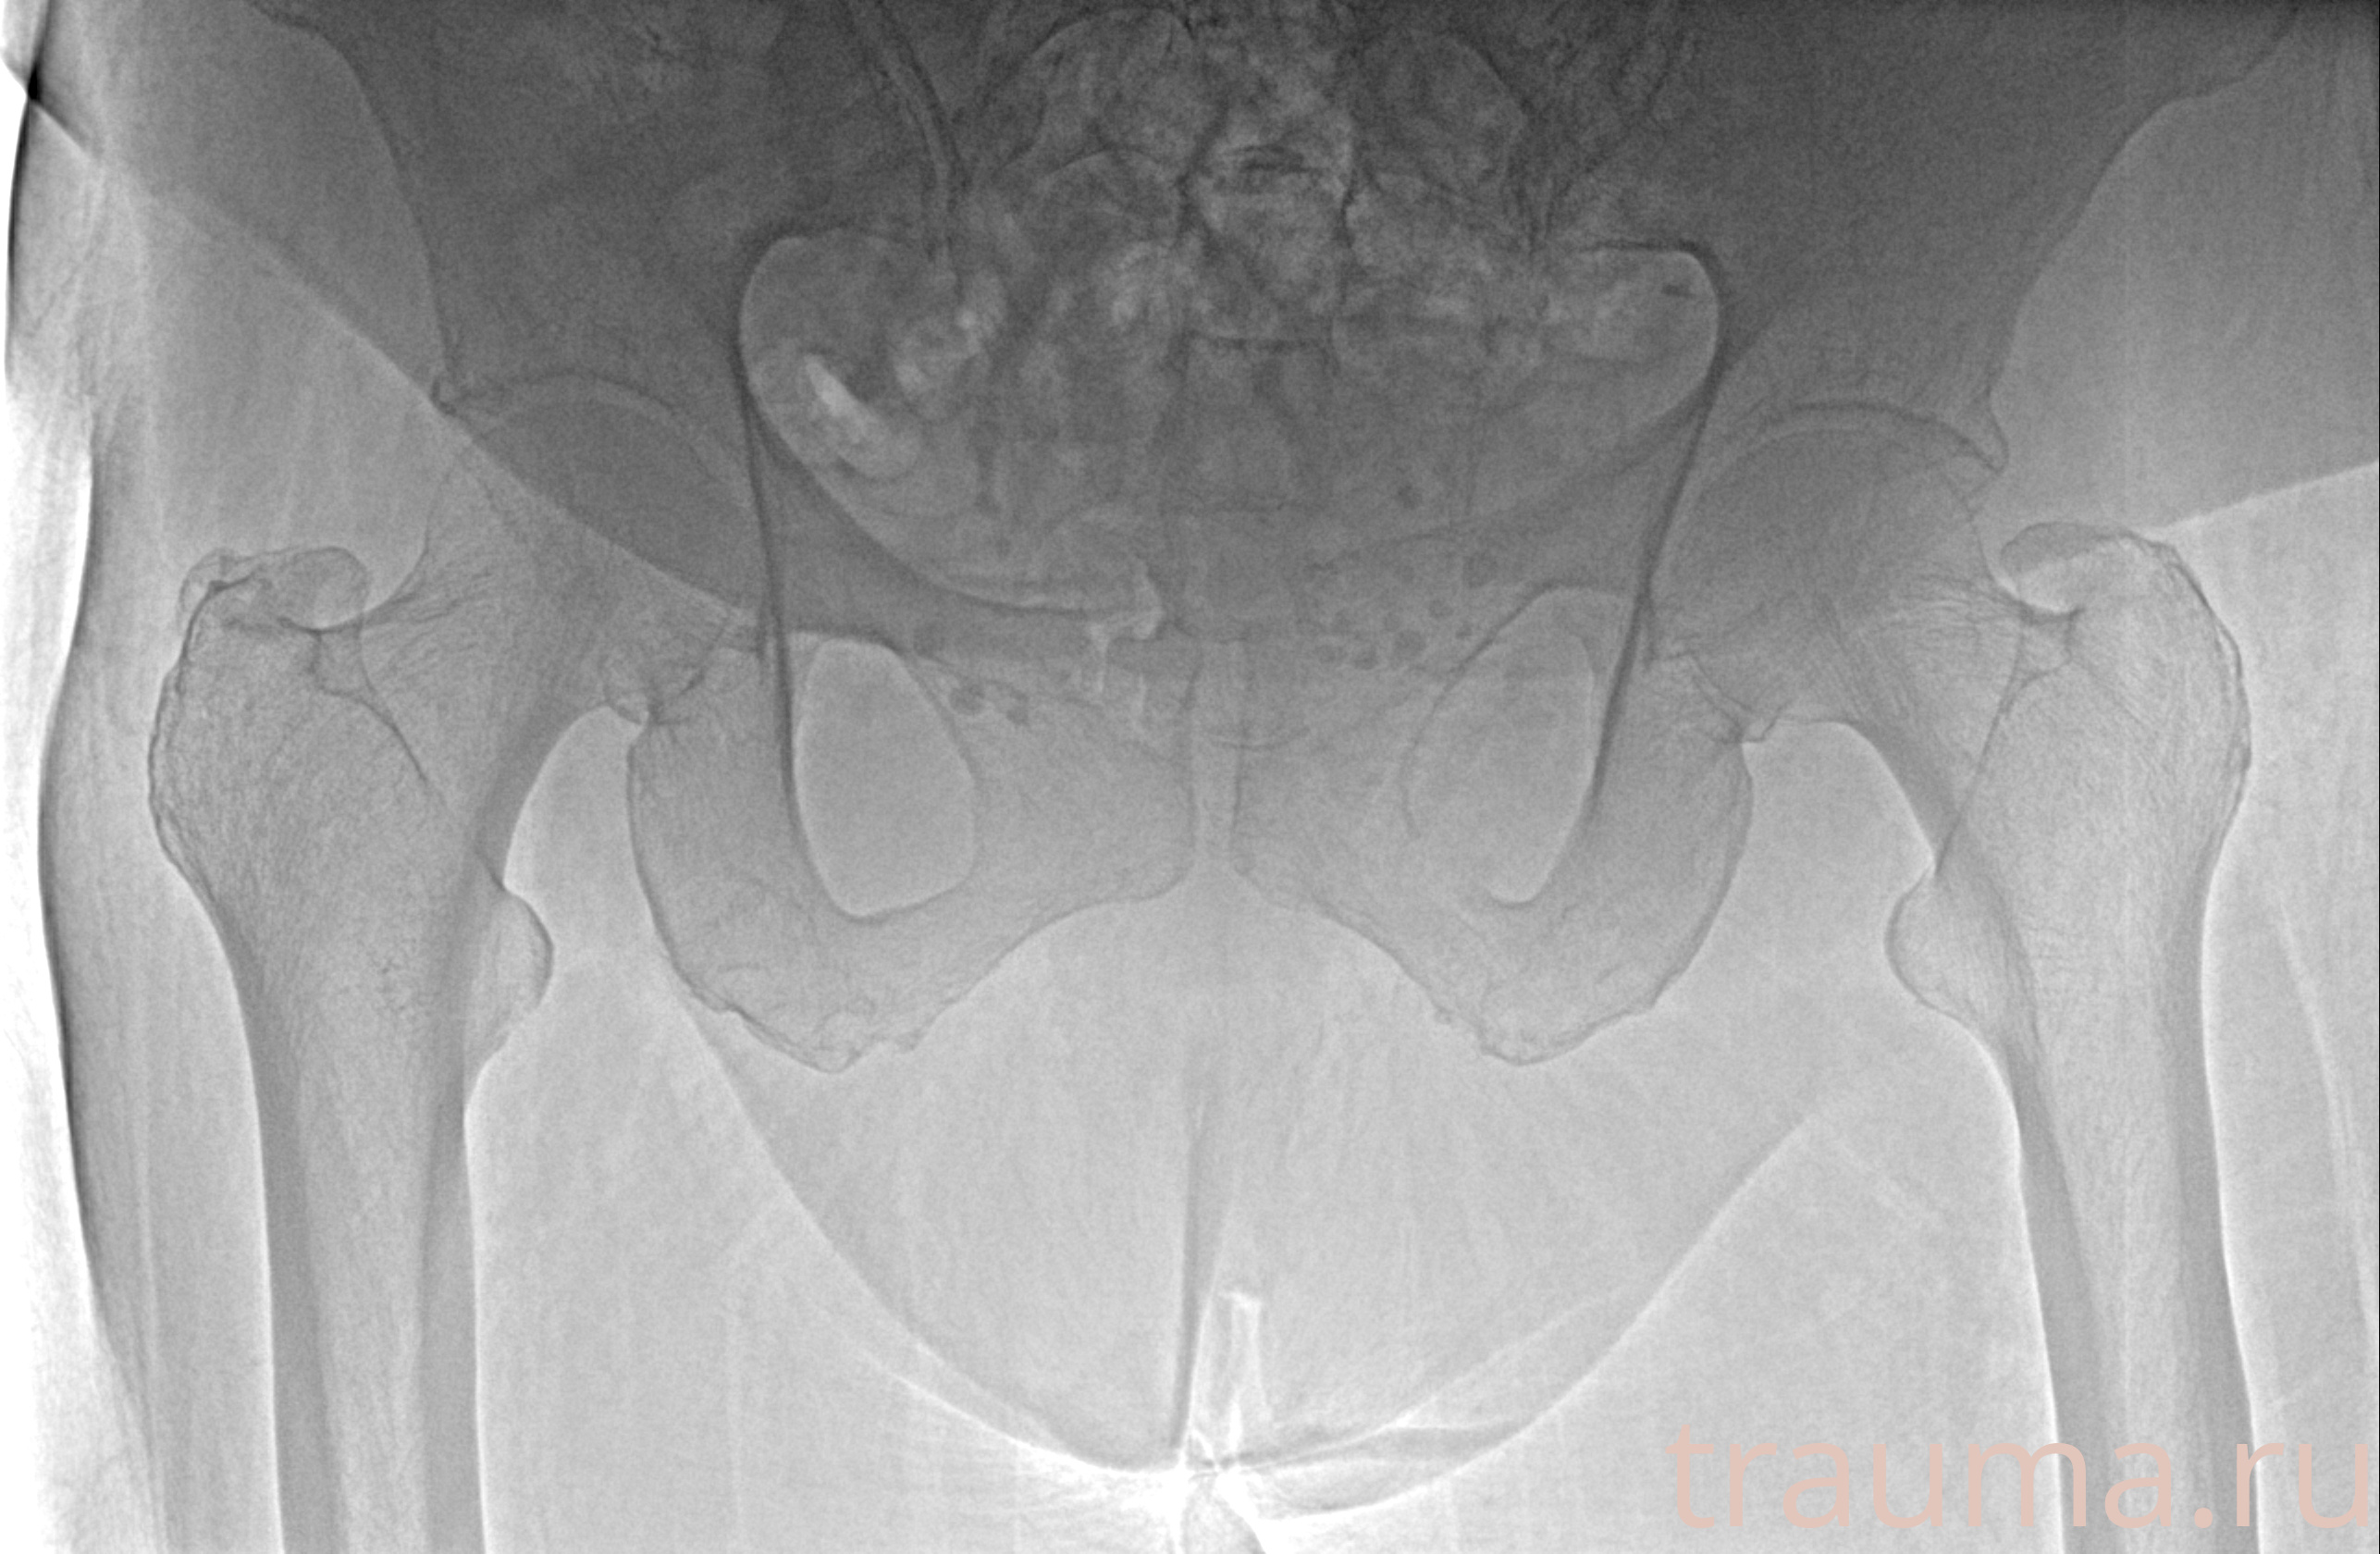

Рентгенограммы

Рентген на дому: по вашему адресу приезжает врач-рентгенолог, травматолог-ортопед с мобильным рентгеновским аппаратом, проводит диагностику травмы или заболевания, делает необходимые рентгенограммы, дает рекомендации по дальнейшему лечению. Получить качественные снимки в домашних условиях возможно благодаря уникальной методике, разработанной МосРентген Центром для института  Склифосовского